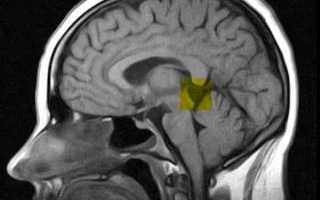

Кисты могут образоваться в различных участках и органах тела человека. Исключение не составляет головной мозг. Кисты головного мозга делятся по типу ткани, из которой они образовываются. Самыми распространенными из них являются арахноидальная, коллоидальная, дермоидная, эпидермоидная, пинеальная. В шишковидной железе головного мозга возникает пинеальная киста. Обнаружить ее можно совершенно случайно. Например, при прохождении магнитно-резонансной томографии по поводу совершенно другого заболевания.

Как правило, кисты шишковидной железы головного мозга диагностируются при проведении компьютерной томографии (КТ) или магнитно-резонансной томографии (МРТ) головного мозга. Такие исследования позволяют определить размеры и форму кисты, а также ее содержимое. В большинстве случаев, если киста не вызывает симптомов и не растет, не требуется никакого лечения.

1. Компьютерная томография (КТ) и магнитно-резонансная томография (МРТ) – данные методы позволяют получить детальные снимки головного мозга, на которых можно увидеть кисту и оценить ее размеры и местоположение. КТ и МРТ также полезны для исключения других возможных причин симптомов пациента.